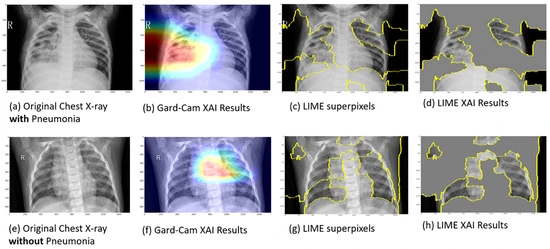

The need for transparency has led to the development of explainable AI models, which reveal the reasoning behind predictions. Grad-CAM, LIME, and SHAP are examples of such models.

Grad-CAM highlights the regions of an image that most influenced a prediction, LIME analyzes how small changes in input affect the outcome, and SHAP assigns contribution scores to different features. These methods help users understand whether the AI model is focusing on meaningful patterns or being misled by noise, turning complex outputs into insights that are easier to trust.

A recent study showcased how such tools are being applied in healthcare. Heatmaps from Grad-CAM, LIME, and SHAP were used to support doctors in detecting pneumonia from chest X-rays and identifying breast cancer in mammograms. By comparing AI reasoning with medical evidence, doctors can confirm whether an AI system is helping or making mistakes.

An Example of Explainable AI in Pneumonia Detection from Chest X-rays (Source)